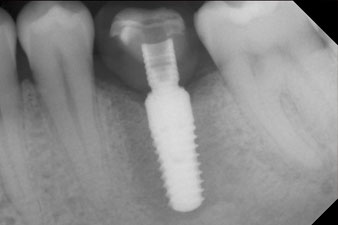

Nach Abheilung der Weichgewebe wurde vor der weiteren prothetischen Versorgung die Implantatstabilität erneut bestimmt.

Beide Werte waren praktisch unverändert und lagen im Übergang vom mittleren in den hohen Bereich – wobei der niedrigere Wert immer als therapiebestimmende Referenz dient.

Damit konnten eine erfolgreiche Osseointegration und ausreichende biologische Stabilität dokumentiert werden, die eine Abformung in derselben Sitzung erlaubte.